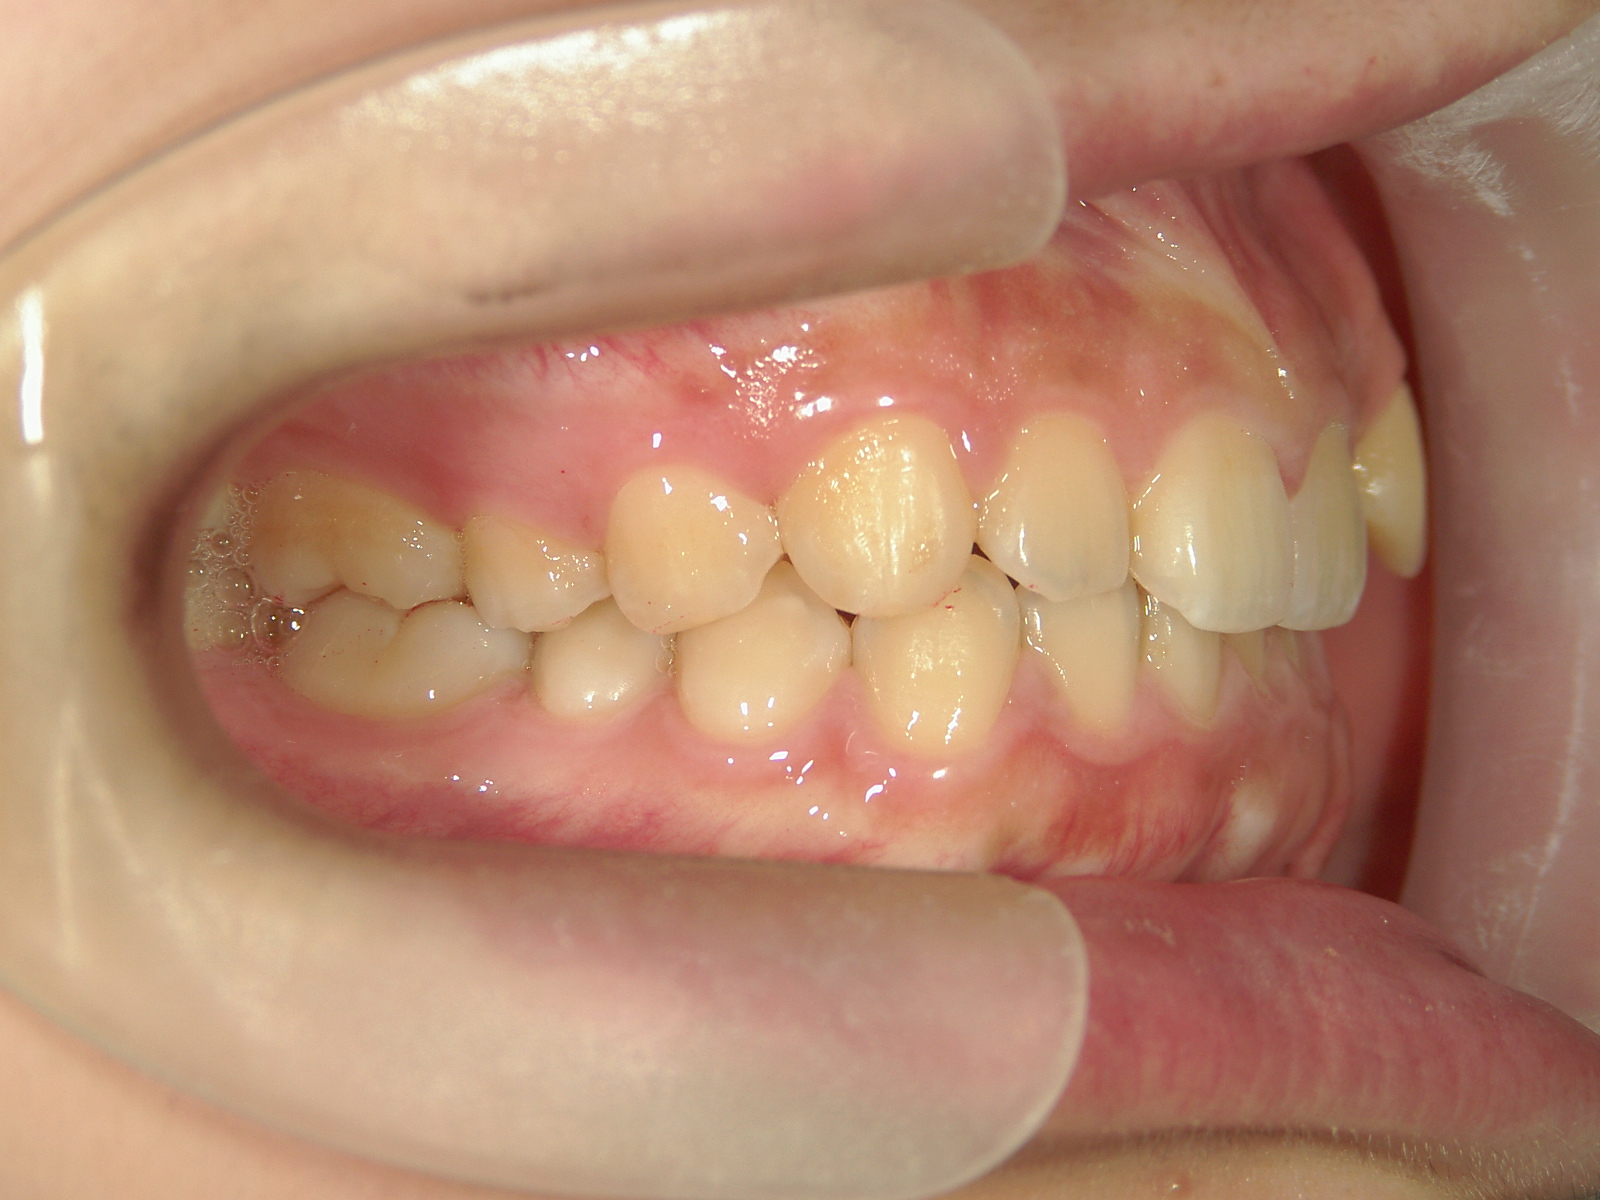

インビザライン矯正 症例(19)

主訴: 左上犬歯が出ているのが気になる

Ⅱ級ゴムを併用。